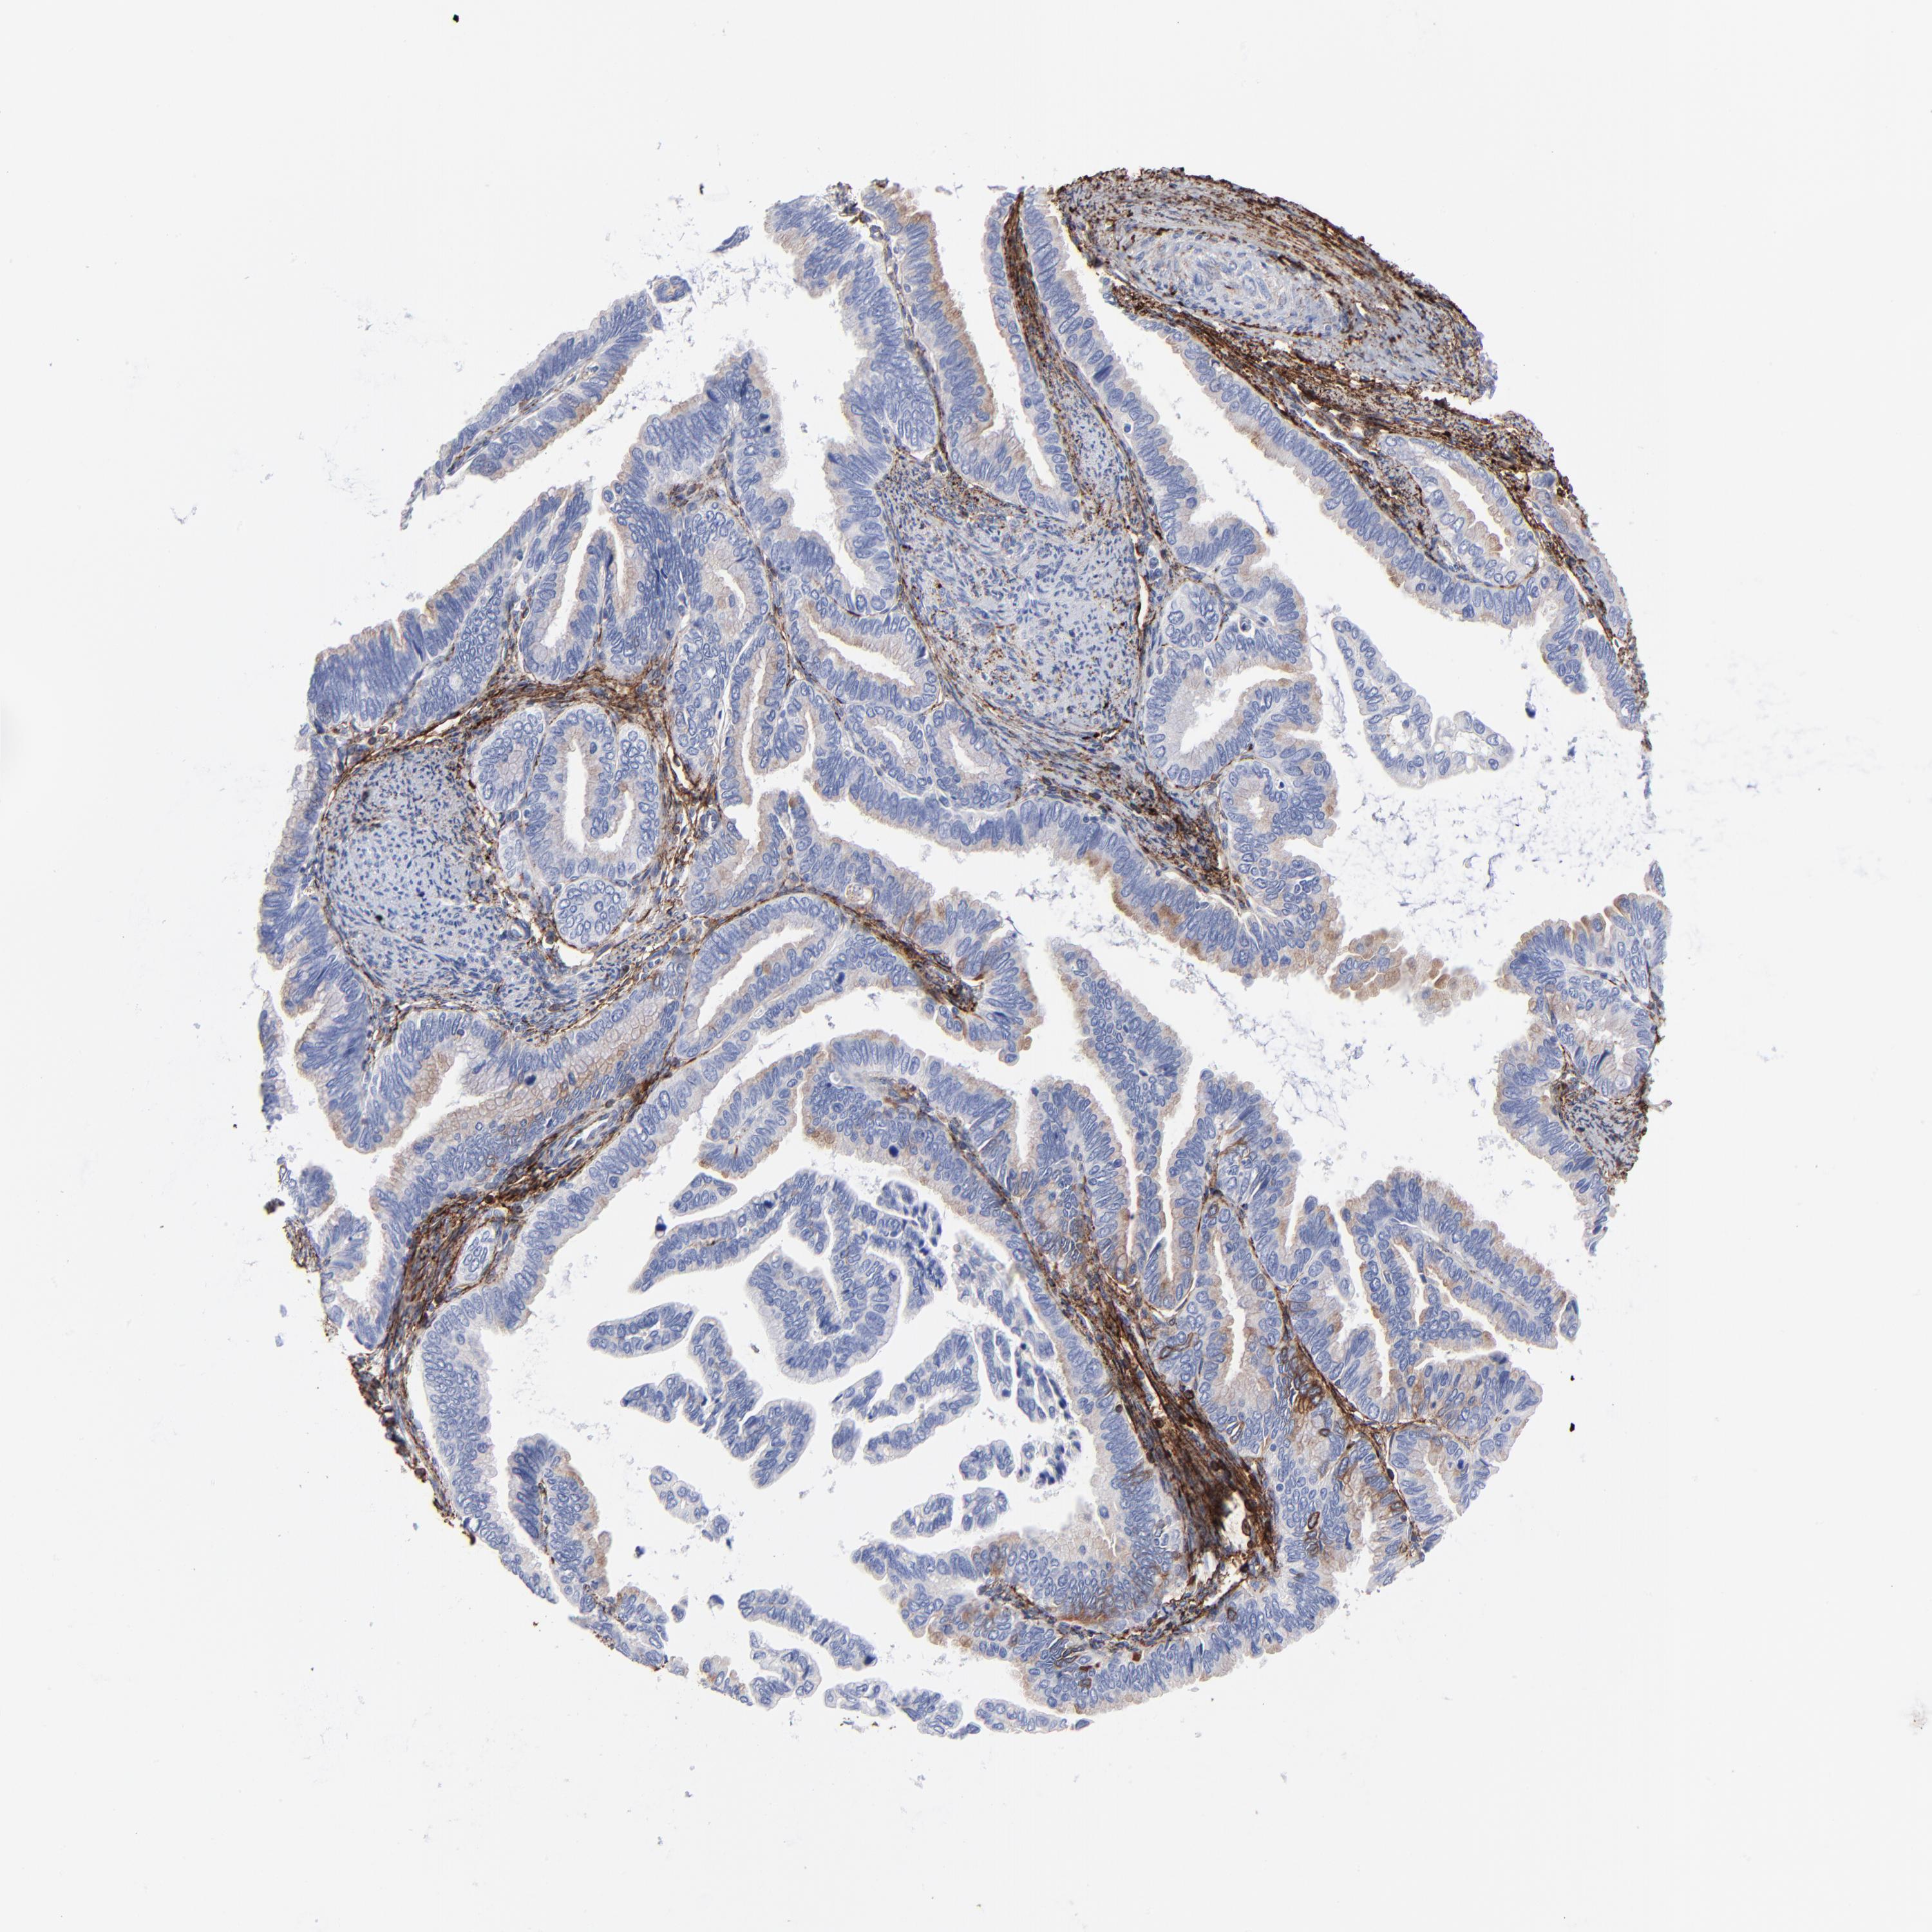

CERVICAL CANCER - Protein expressioni

A mouse-over function shows sample information and annotation data. Click on an image to view it in a full screen mode. Samples can be filtered based on level of antibody staining by selecting one or several of the following categories: high, medium, low and not detected. The assay and annotation is described here.

Note that samples used for immunohistochemistry by the Human Protein Atlas do not correspond to samples in the TCGA dataset.

Antibody stainingi

Antibody staining in the annotated cell types in the current human tissue is reported as not detected, low, medium, or high, based on conventional immunohistochemistry profiling in selected tissues. This score is based on the combination of the staining intensity and fraction of stained cells.

Each image is clickable and will lead to virtual microscopy that enables deeper exploration of all samples and also displays staining intensity scores, fraction scores and subcellular localization as well as patient and tissue information for each sample.

Antibody HPA001934

Antibody CAB018622

Adenocarcinoma, NOS

Squamous cell carcinoma, NOS